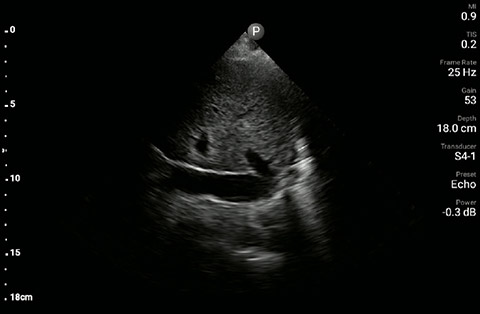

The patient had reduced LV systolic function without new or severe valvular pathology, a dilated, non-collapsing IVC, and diffuse B lines (left greater than right) on lung ultrasound imaging.

Inferior vena cave

In the interim, while awaiting laboratory results and chest X-ray imaging, POCUS with a three-point exam (F-TTE, IVC collapsibility, and lung ultrasound) was used for bedside evaluation of the etiology of the patient’s dyspnea. Within minutes, and with the additive information from the combined cardiac, subcostal IVC, and lung ultrasound imaging, the patient was diagnosed with acute on chronic congestive heart failure and flash pulmonary edema as the cause of his respiratory distress and hypoxia.